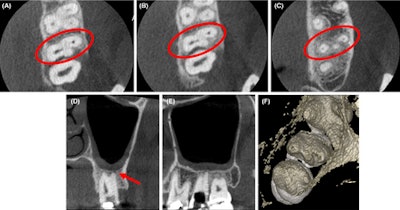

(A-C) Axial CBCT images in the cervical, middle, and apical region of the man’s molar. (D) The coronal section showed the apical split of roots and early periapical radiolucency in the palatal root (red arrow). (E) The sagittal section shows the gouging of the floor.

Also, the CBCT images confirmed that the distobuccal canal was adjacent to the palatal orifice. The scan further revealed that the coronal section of the tooth had early periapical radiolucency in the palatal root, which was not visible on the early images, the authors wrote.